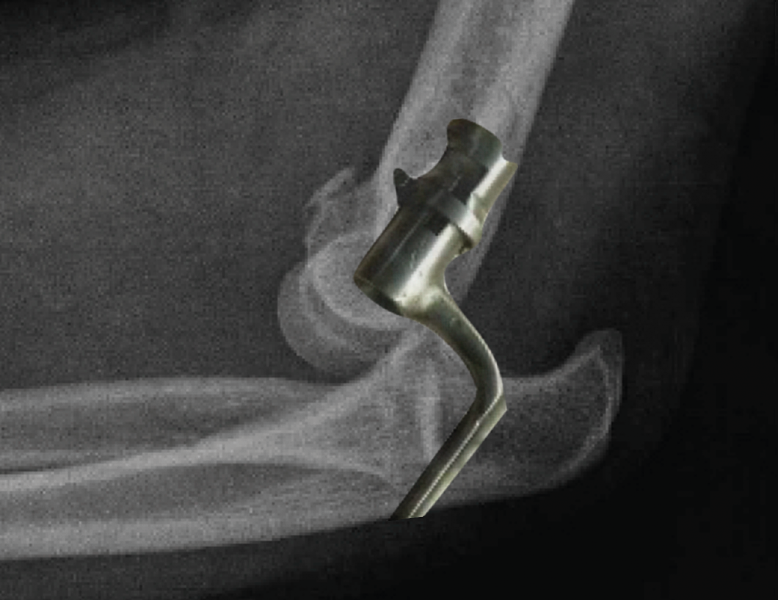

Figura 5. Radiografías simples de codo en proyección anteroposterior y lateral. En estas radiografías puede apreciarse una luxación posterolateral de un codo izquierdo, además de fractura de la cabeza del radio y fractura de la punta de la coronoides.